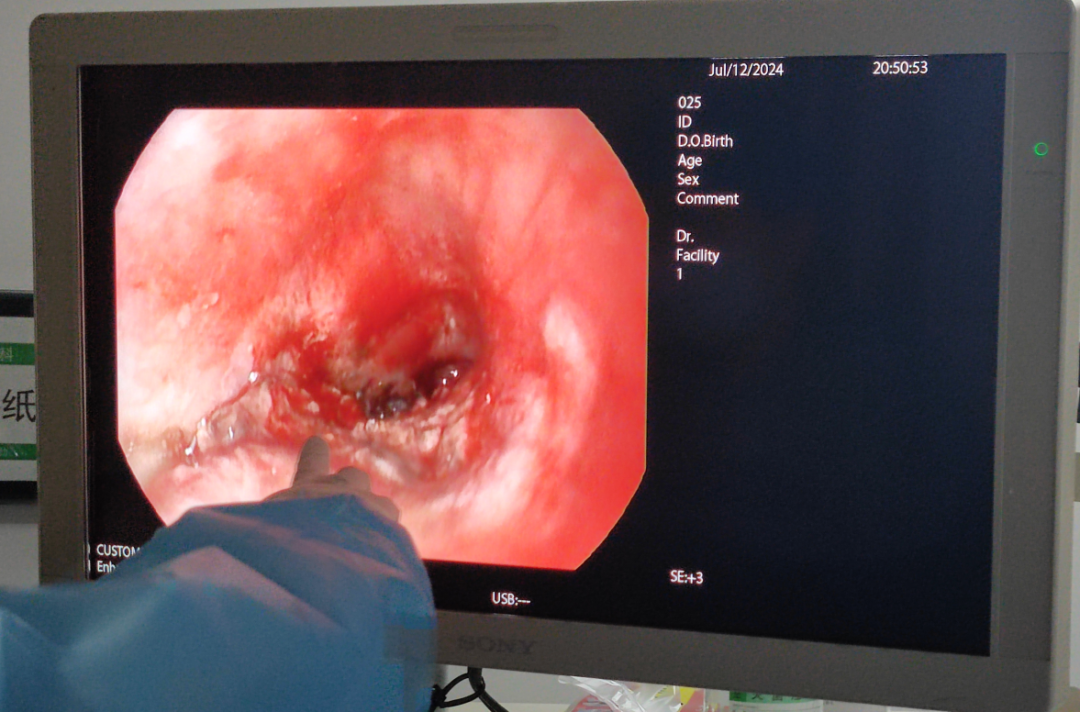

气管镜可见肿瘤不完全阻塞总气道

术前气管镜下见肿瘤严重阻塞总气道